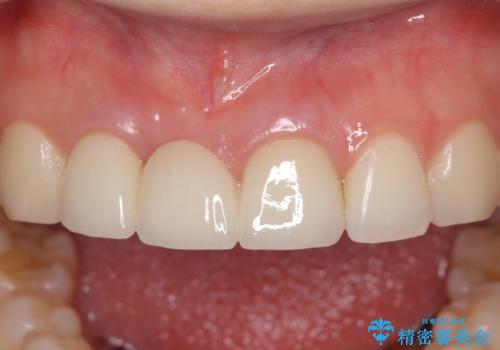

歯肉から血が 前歯のオールセラミックブリッジの再製作

- 他院で装着したばかりの前歯のブリッジが気に入らず、作り替えを希望して来院された患者様です。

前院では、土台の金属を除去することは不可能であると言われたとのことでした。金属の土台が残っているとセラミックにグレーの金属色が透けて見えてしまうため、拡大鏡やマイクロスコープを用いて丁寧に除去し、天然歯の色に近いファイバーコアを植立することとしました。

また、歯とクラウンの境目が合っていない部分が多く、歯肉からの出血が認められました。

金属色の透けた感じも歯肉からの出血もなくなり、自然な仕上がりの前歯となったので、患者様には大変満足していただきました。